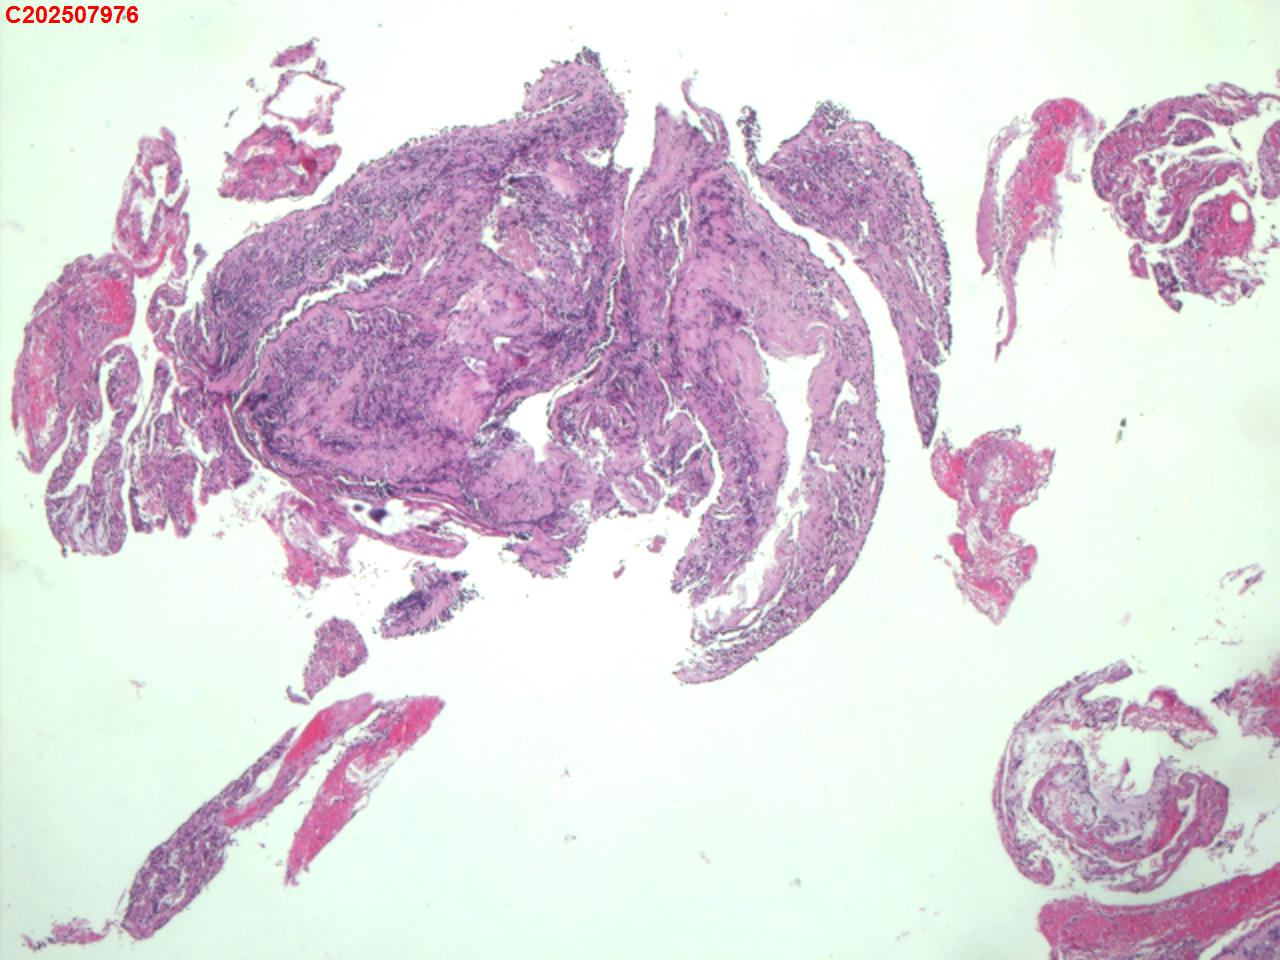

右肺上叶开口处 气管镜咬检

右肺上叶开口上缘处可见肉芽增生,予咬检。

感觉:炎性纤维组织增生